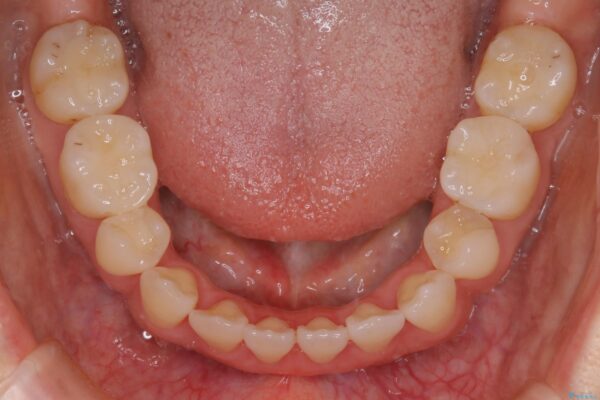

抜歯矯正

歯のガタつきの度合いが強い場合や、上下で大きく噛み合わせがズレている時などに、その改善のための大きなスペースを作る代表的手段が「抜歯」です。

一般的には第一小臼歯(犬歯の一つ隣の歯)を抜くことが多く、前歯のガタつきを改善したり口元を引っ込める場合に利用されます。

オープンバイト

臼歯の位置が高く噛んだ時に奥歯しか当たらなかったり、舌癖などが原因で前歯が前に倒れてしまうことで上下の前歯の被蓋がなくなってしまっている状態をオープンバイトといいます。前者の場合は臼歯を圧下し沈めてあげることで改善させます。後者の場合は前方に傾斜している歯を元の角度に戻してあげることで改善しますが、舌癖がある場合はその癖自体を無くす治療をしない限りまた同じ状態へと後戻りしてしまいます。